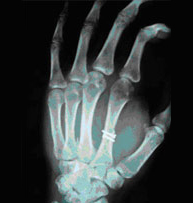

Fractures of the metacarpals and phalanges account for 10% of all fractures. More than half are due to occupational injuries. It is unquestionable the importance of a hand in our daily life and it goes without saying that proper recovery requires an exquisite knowledge of anatomy and biomechanics in order to properly treat hand injuries. Stiffness is very common in lengthy immobilizer treatments. To avoid stiff joints we propose minimally invasive techniques that allow early reincorporation in daily activities.